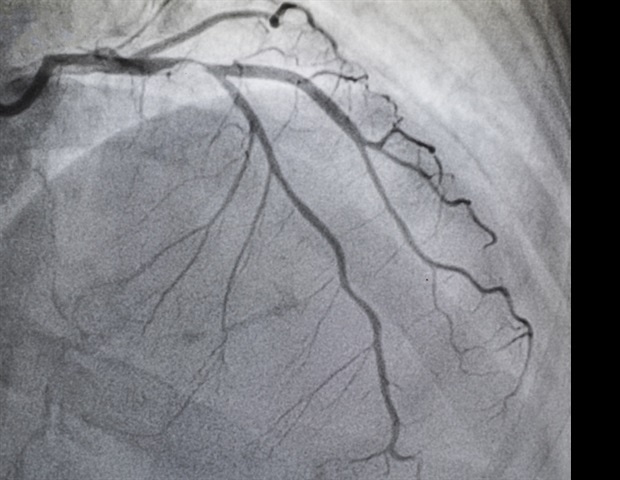

Η αορτική στένωση είναι μια από τις πιο συνηθισμένες και σοβαρές ασθένειες των βαλβίδων της καρδιάς, επηρεάζοντας περισσότερους από 2,5 εκατομμύρια Αμερικανούς άνω των 75 ετών. Η ασθένεια αυτή προκαλεί τη συσσώρευση ασβεστίου, περιορίζοντας τη ροή του αίματος και οδηγώντας σε συμπτώματα όπως δύσπνοια, κόπωση και δυσκολίες στην κίνηση, που συχνά παρανοούνται ως φυσικά σημάδια γήρανσης. Παρά την ύπαρξη θεραπειών, μόλις το 50% των ασθενών με σοβαρή AS υποβάλλονται σε AVR.

Η έρευνα, γνωστή ως DETECT-AS, είναι μια πρακτική, κλινική δοκιμή που διεξήχθη σε πολλαπλά ιατρικά κέντρα. Συμμετείχαν 285 ιατροί και 939 ασθενείς με σοβαρή AS. Οι συμμετέχοντες διαχωρίζονταν σε τρεις ηλικιακές ομάδες: κάτω των 65 ετών, 65-80 ετών και άνω των 80 ετών. Όλοι οι ασθενείς υποβλήθηκαν σε υπερηχοκαρδιογράφημα, και οι γιατροί τους έλαβαν ειδοποιήσεις όταν τα αποτελέσματα απέδιδαν AS.